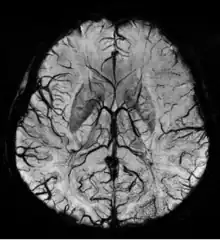

Susceptibility weighted imaging (SWI), originally called BOLD venographic imaging, is an MRI sequence that is exquisitely sensitive to venous blood, hemorrhage and iron storage. SWI uses a fully flow compensated, long echo, gradient recalled echo (GRE) pulse sequence to acquire images. This method exploits the susceptibility differences between tissues and uses the phase image to detect these differences. The magnitude and phase data are combined to produce an enhanced contrast magnitude image. The imaging of venous blood with SWI is a blood-oxygen-level dependent (BOLD) technique which is why it was (and is sometimes still) referred to as BOLD venography. Due to its sensitivity to venous blood SWI is commonly used in traumatic brain injuries (TBI) and for high resolution brain venographies but has many other clinical applications. SWI is offered as a clinical package by Philips and Siemens but can be run on any manufacturer’s machine at field strengths of 1.0 T, 1.5 T, 3.0 T and higher.

SWI uses a fully velocity compensated, RF spoiled, high-resolution, 3D gradient recalled echo (GRE) scan. Both the magnitude and phase images are saved, and the phase image is high pass (HP) filtered to remove unwanted artifacts. The magnitude image is then combined with the phase image to create an enhanced contrast magnitude image referred to as the susceptibility weighted (SW) image. It is also common to create minimum intensity projections (mIP) over 8 to 10 mm to better visualize vein connectivity. In this way four sets of images are generated, the original magnitude, HP filtered phase, susceptibility weighted, and mIPs over the susceptibility weighted images.

The susceptibility weighted image is created by combining the magnitude and filtered phase images. A mask is created from the phase image by mapping all values above 0 radians to be 1 and linearly mapping values from -π to 0 radians to range from 0 to 1, respectively. Alternatively, a power function (typically 4th degree) can be used instead of a linear mapping from -π to 0 to increase the effect of the mask. The magnitude image is then multiplied by this mask. In this way phase values above 0 radians have no effect and phase values below 0 radians darken the magnitude image. This increases the contrast in the magnitude image for objects with low phase values such as veins, iron, and hemorrhage.